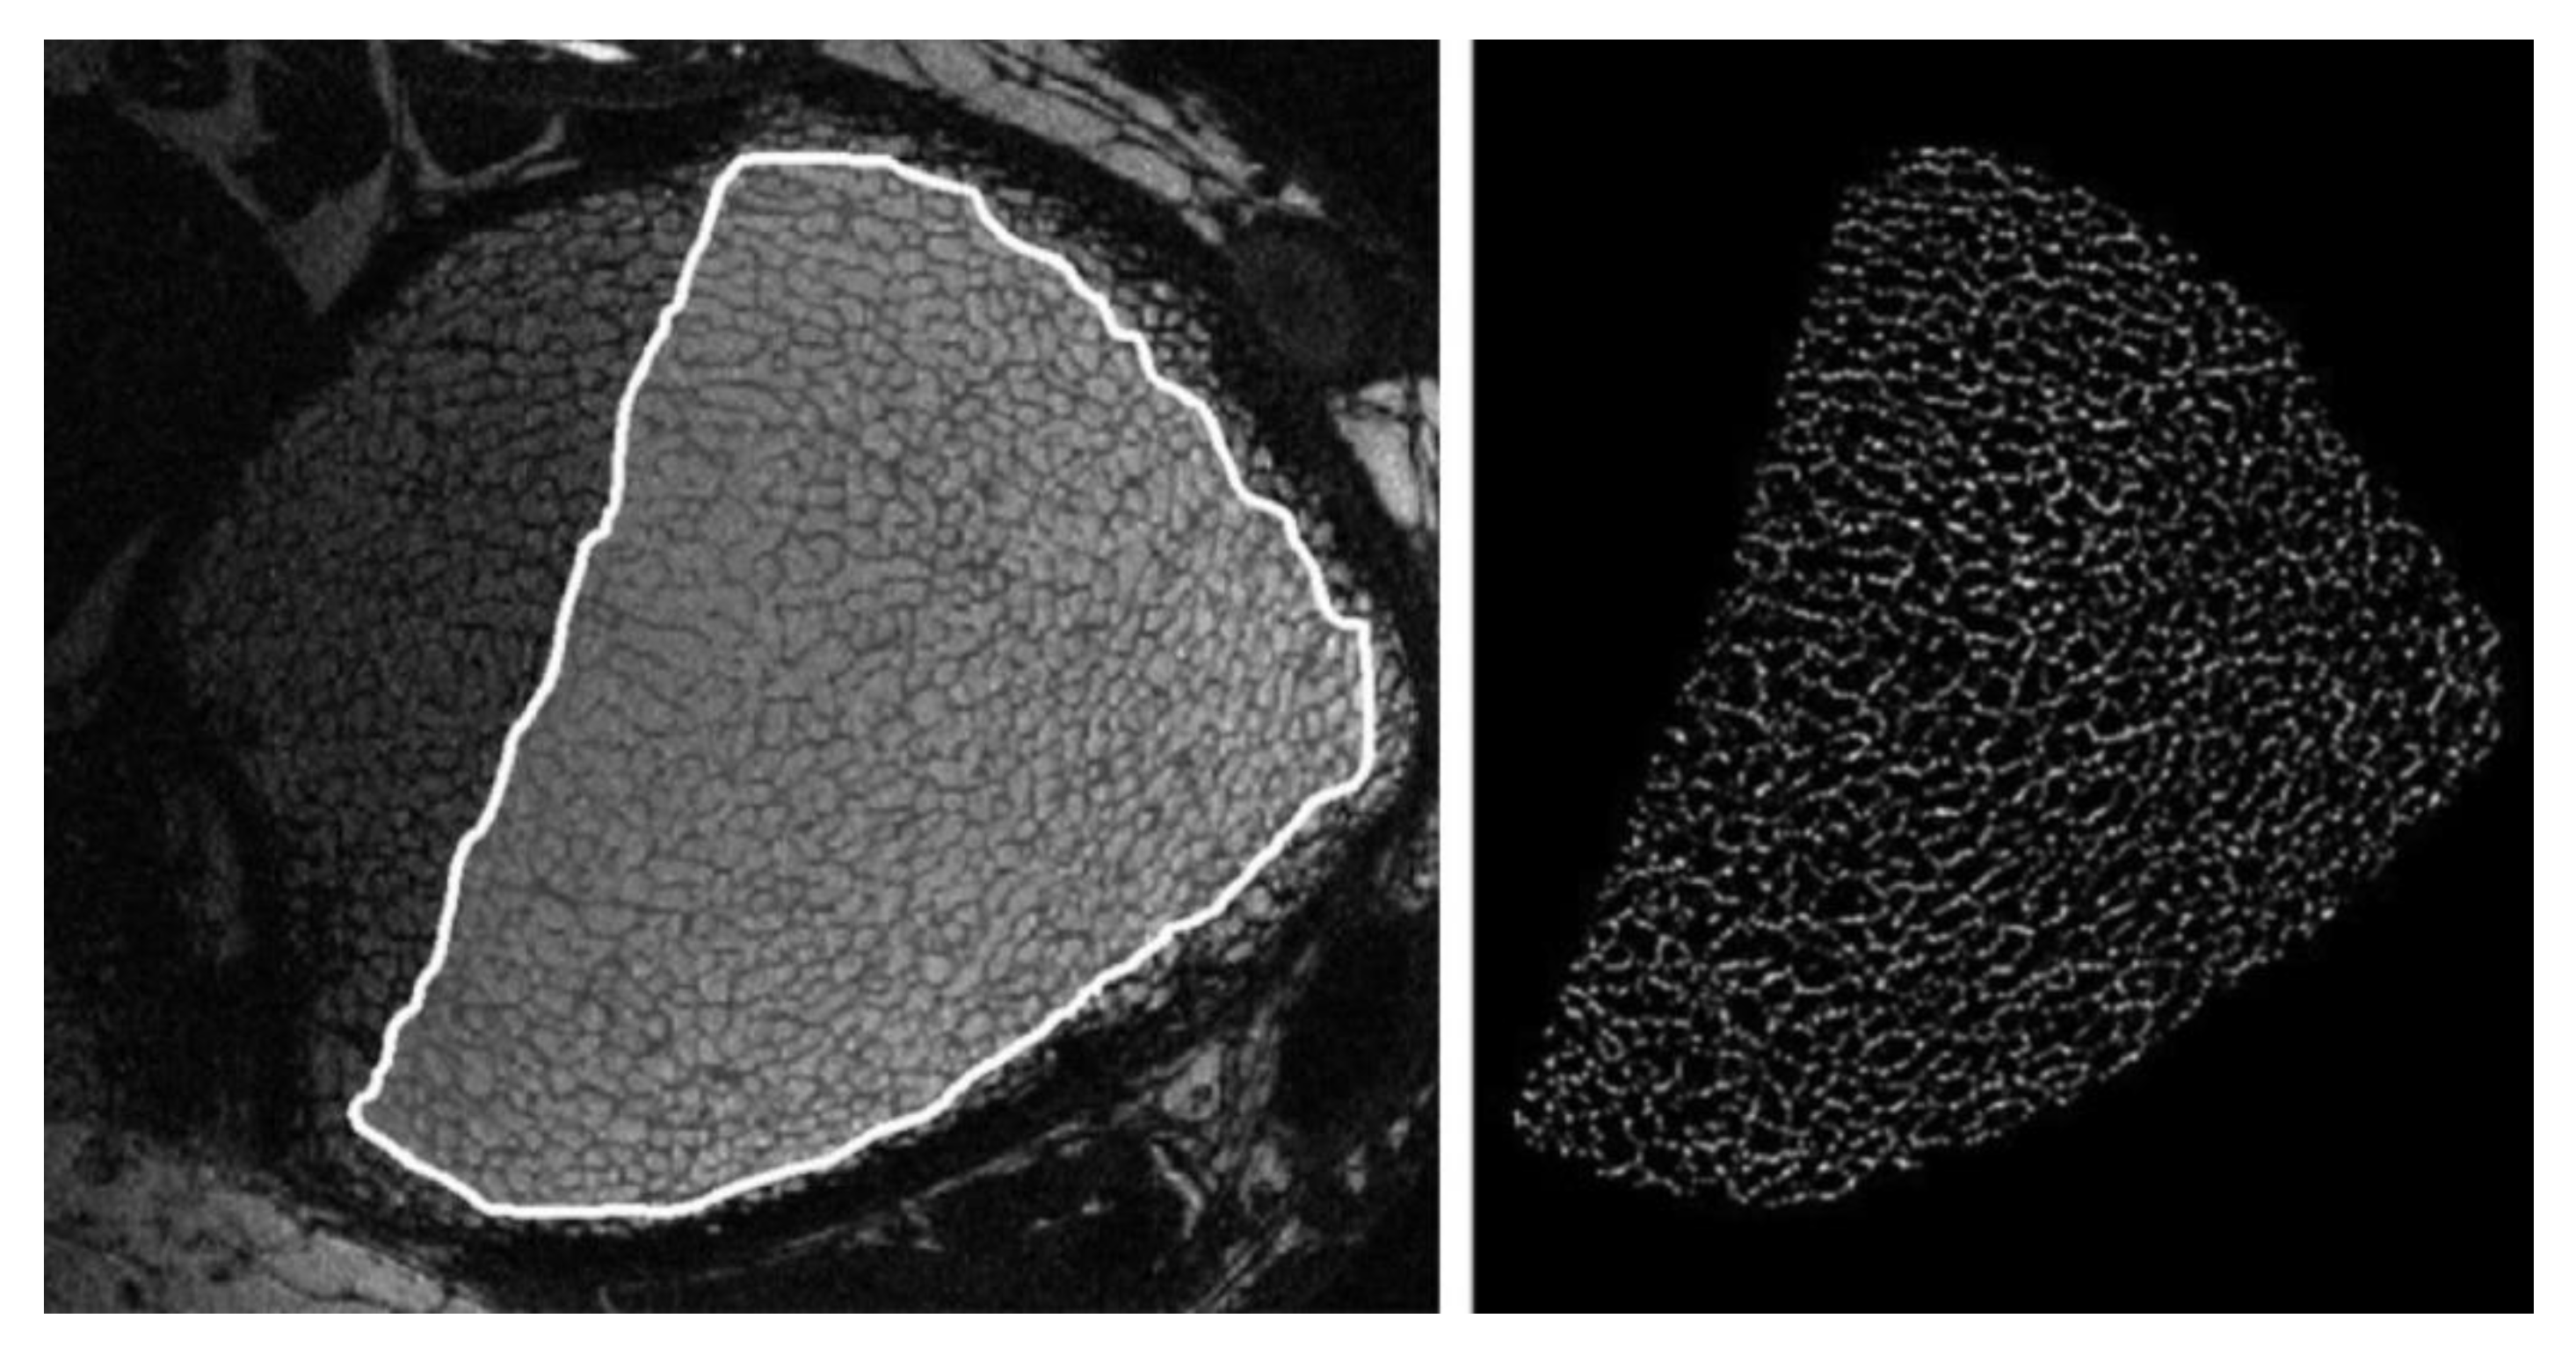

Trabecular bone is composed of numerous plate-like and rod-like trabeculae that arrange themselves according to the applied mechanical stress; their relative proportion depends on the bone site (Figure 3). In general, plates align along the longitudinal axis of bone and sustain most of the load, while rods are disposed along the transverse plane and act as links to stabilise the structure [29].

Figure 3.

Rod and plate distribution in a human humeral head (3D rendering executed by the authors by scanning the bone sample with a micro-computed tomographer at a resolution of 3 µm).

Chen and Kubo [22] observed an increase in the rod-like proportion with ageing and OP due to the conversion of plate-like trabeculae into rod-like ones in several human bone sites (vertebra, femur and distal radius). Gentzsch and collaborators [30] tried to explain this conversion mechanism by monitoring the resorption lacunae present on the trabecular compartment of various femoral heads of cadavers, concluding that the centre of trabecular plates is a preferential site for the formation of resorption lacunae. In the presence of a continuous erosion process not counterbalanced by an effective bone matrix refilling by Ob, the resorption cavities deepen and develop into plate perforations, leading to the final conversion of plates into rods. Since resorption lacunae and plate perforations represent discontinuities in the bone structure, they are preferential regions of microfracture triggering, leading to an overall reduction of bone resistance to the applied loads.

A common indicator used in bone research studies to determine the balance between rods and plates is the structure model index (SMI), exploiting the measurement of the bone surface curvature. Ideally, the SMI value is zero for a plate and three for a cylinder, therefore, the variation of bone SMI between these extremities can indicate the prevalence of one trabecular structure over another. Considering that in the osteoporotic bone a conversion of trabecular plates in rods is normally observed, superior values of SMI are usually reported compared to those registered for the healthy tissue [31].